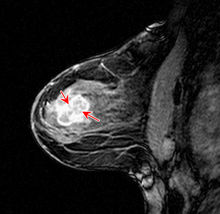

乳腺外科

乳腺癌我院乳腺外科,對乳腺良惡性疾病的診治預防工作居於國內領先水平,在國內率先開展了

以立體定位等方法進行的乳腺癌的早期發現研究,首先套用了乳腺癌的中心象限保乳術以及環乳暈切口的多腫瘤切除。對於乳腺癌的治療形成一體化全程治療,包括手術、化療、內分泌藥物及靶向藥物治療,治療規範、手術併發症遠低於平均水平,是“北京市乳腺癌治療路徑”制定單位。對於良性腫瘤及乳頭溢液等病變採用微創入路或隱蔽切口手術,治療徹底、注重美觀。目前正在主持多項國家級科研項目。